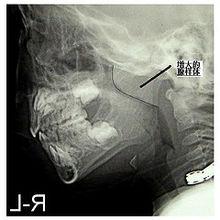

腺樣體增大的診斷主要是拍X線鼻咽部側位片,因為進行鼻咽鏡和鼻咽部指診的檢查很難取得兒童的合作,而且還不能準確測量鼻咽腔的寬度和阻塞的程度。要做好腺樣體的測量,就需要拍一張高質量的X光片,那么怎么樣拍鼻咽部側位片呢?

鼻咽部側位片的投照方法:病人取坐位或站立側位,頭部略上抬,使眶耳線平行於地面,矢狀面與暗盒平行,中心線通過外耳孔前方和下方各2厘米處,膠片距在120CM左右。

測量方法:1.腺樣體厚度的測量:腺樣體最突點至枕骨斜坡顱骨外側面的垂直距離為腺樣體厚度:

圖1;2.腺樣體長度的測量:使用平行曲線法,沿C3椎體前軟組織前緣向上劃與頸椎相平行的直線,上行至軟齶後下緣,水平轉折向前向上劃與軟齶後上緣平行的弧線至硬齶後部,此線與突入鼻咽腔的腺樣體後、前緣相交為B、A兩點,AB間距為腺樣體長徑

增殖腺3.鼻咽通氣道的寬度:硬齶後端至翼板與顱底交點間的距離為鼻咽通氣道的寬度。

增殖腺(圖3)

以腺樣體厚度與鼻咽通氣道的寬度的比值(A/N)可判斷腺樣體的肥大程度:0.5-0.6為正常;0.61-0.70為中度肥大;0.71以上為病理性肥大。腺樣體肥大多與齶扁桃體炎同時存在,X線片上顯示齶扁桃體肥大、後突,口咽腔氣道變窄.

下面是X線圖片:

增殖腺2.關於A/N比值的問題:用A/N比值的方法比直接測量腺樣體厚度的方法更科學,更有效.但有人將狹窄的鼻咽腔氣道(腺樣體增大壓迫所致)當成鼻咽通氣道的寬度,這是錯誤的。鼻咽通氣道的寬度應為:硬齶後端至翼板與顱底交點間的距離。如圖3